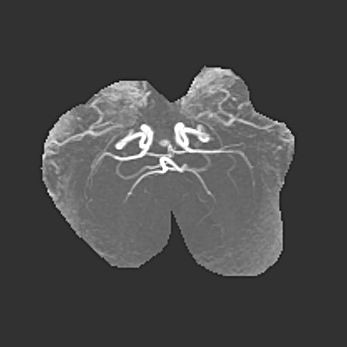

Наружная гидроцефалия с возможной атрофией височных областей.

Возраст: 28 дней

Вес: 3670 г

Пол: мужской

Окружность головы: 38 см

Срок гестации: 40 недель

Гидроцефалия головного мозга у новорожденных – это заболевание, которое характеризуется скоплением избыточного количества спинномозговой жидкости в желудочковой системе головного мозга в результате затруднения её перемещения от места выработки к месту поглощения в кровеносную систему или вследствие нарушения абсорбции. При открытой наружной форме гидроцефалии у новорожденных расширяются и переполняются субарахноидные пространства.

При нормотензивных  формах,  которые,  как  правило,  являются  следствием  перенесенных ишемических  повреждений  паренхимы  мозга,  возможно  сочетание микроцефалии  с нормотензивной гидроцефалией. В основе данных изменений лежит атрофия больших полушарий с преимущественной  локализацией  в  лобно-височных  областях.